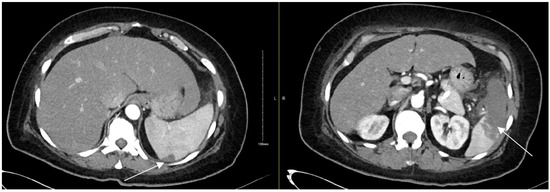

2. Case Presentation